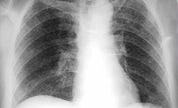

Dat meldt het AD na informatie van de GGD Midden-Nederland. De man waarbij open tbc is aangetroffen, wordt momenteel thuis behandeld. Bij de mensen met wie hij vaak contact heeft, is onderzoek verricht. Volgens de GGD is bij zeven van hen niet-besmettelijke tbc aangetroffen.